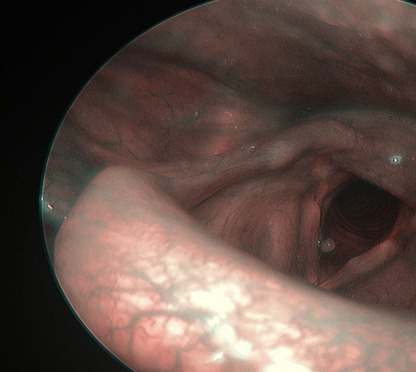

Ses kısıklığı, ses tellerinin düzgün titreşememesi sonucu oluşan, çoğu zaman geçici ancak bazen ciddi hastalıkların da belirtisi olabilen yaygın bir şikâyettir. Özellikle uzun süren (2 haftadan fazla devam eden) ses kısıklıkları mutlaka bir KBB doktoru tarafından değerlendirilmelidir. Ses Kısıklığının En Yaygın Nedenleri 1. Üst Solunum Yolu Enfeksiyonları Grip, soğuk algınlığı ve larenjit gibi enfeksiyonlarda ses telleri şişer ve ses kısıklığı ortaya çıkar.Belirtiler: Boğazda yanma, ağrı, öksürük, sesin çatallanması. 2. Aşırı Ses Kullanımı Öğretmenler, çağrı merkezi çalışanları, şarkıcılar ve gün içinde çok konuşan kişilerde sık görülür.Sürekli bağırmak, yüksek sesle konuşmak veya yanlış ses tekniği kullanmak ses tellerini zorlar. 3. Reflü (Laringofarengeal Reflü) Mide asidinin ses tellerine ulaşması ses kısıklığının sık görülen nedenlerindendir.Belirtileri: Sabah ses kısıklığı, boğazda gıcık hissi, sık boğaz temizleme ihtiyacı. 4. Alerjiler Alerjik reaksiyonlar ses tellerinde ödem oluşturabilir.Polen, toz veya kimyasal kokulara duyarlılığı olan kişilerde daha sık görülür. 5. Sigara ve Zararlı Kimyasallar Sigara içmek ses tellerini tahriş eder, uzun vadede kalıcı hasarlara ve ciddi hastalıklara yol açabilir.Ayrıca dumanlı, tozlu veya kimyasallarla dolu ortamlarda çalışmak risk artırır. 6. Ses Teli Nodülleri ve Polipleri Ses tellerinin fazla zorlanması sonucu oluşan iyi huylu oluşumlardır.Özellikle uzun süre geçmeyen kısıklıklarda nodül olasılığı yüksektir. 7. Tiroid Problemleri Tiroid bezinin az çalışması sesin kalitesini etkileyebilir.Kısık, yorgun ses ve boğazda baskı hissi görülebilir. 8. Nörolojik Problemler Çok nadir olsa da sinir sistemi kaynaklı rahatsızlıklar ses tellerinin hareketini etkileyebilir. Ses Kısıklığı Nasıl Geçer? 1. Sesin Dinlendirilmesi Bağırmaktan, yüksek sesle konuşmaktan ve fısıltı yapmaktan kaçınmak gerekir.Fısıltı, ses tellerine normal konuşmadan daha çok yük bindirir. 2. Bol Su İçmek Ses tellerinin nemli olması iyileşmeyi hızlandırır. Günde en az 1,5–2 litre su önerilir. 3. Buhar ve Nemlendirme Sıcak duş buharı veya odada nemlendirici cihaz kullanmak ses tellerinin rahatlamasına yardımcı olur. 4. Reflü Tedavisi Reflüye bağlı ses kısıklığında: 5. Alerji Kontrolü Alerjenlerden uzak durmak ve uygun antihistaminik tedavi sesin düzelmesini sağlar. 6. Sigaranın Bırakılması Ses tellerinin iyileşmesi için en önemli adımlardan biridir. 7. KBB Muayenesi ve Gerekirse Endoskopi 2 haftadan uzun süren ses kısıklığında KBB muayenesi şarttır.Endoskopik muayene ile ses telleri doğrudan görüntülenir ve nodül, polip, enfeksiyon gibi durumlar netleşir. Ne Zaman Doktora Başvurmalısınız? Sonuç Ses kısıklığı çoğu zaman basit nedenlerle gelişse de, uzun süre devam eden şikâyetlerde altta yatan ciddi bir problem olabilir. Erken teşhis, hem ses kalitesini korur hem de olası hastalıkların ilerlemesini engeller.

Kulak Burun Boğaz (KBB) muayenesi, kulak, burun, boğaz ve baş-boyun bölgesiyle ilgili sağlık sorunlarının değerlendirilmesi için yapılan kapsamlı bir incelemedir. Bu muayene sayesinde; işitme kaybı, burun tıkanıklığı, geniz akıntısı, ses kısıklığı, boğaz ağrısı, sinüzit veya baş dönmesi gibi birçok problem doğru şekilde teşhis edilir. 🔍 KBB Muayenesi Neden Yapılır? KBB muayenesi; hem rutin kontrollerde hem de hastanın belirli bir şikâyetle başvurması durumunda yapılır.En sık muayene sebepleri şunlardır: Bu şikâyetler, yaşam kalitesini önemli ölçüde etkileyebileceğinden erken tanı büyük önem taşır. 🩹 KBB Muayenesi Nasıl Yapılır? KBB muayenesi genellikle üç temel bölgeyi kapsar: kulak, burun ve boğaz. 👂 Kulak Muayenesi Uzman hekim, otoskop adı verilen özel bir cihazla dış kulak yolunu ve kulak zarını inceler. Gerekli durumlarda işitme testi (odyometri) uygulanarak kulaktaki ses algılama düzeyi değerlendirilir. 👃 Burun Muayenesi Burun içi ve sinüs kanalları endoskopik kamera yardımıyla detaylı şekilde incelenir. Bazı durumlarda sinüs filmi veya tomografi ile detaylı görüntüleme gerekebilir. 👄 Boğaz Muayenesi Ağız, bademcikler, gırtlak ve ses telleri endoskop veya laryngoskop ile kontrol edilir. ⚕️ KBB Muayenesi Ne Kadar Sürer? Genellikle 10–20 dakika arasında tamamlanır.Eğer ileri tetkik veya endoskopik inceleme gerekiyorsa süre uzayabilir.Muayene tamamen ağrısızdır ve hastalar aynı gün günlük yaşamlarına dönebilir. 💡 KBB Muayenesi Öncesinde Dikkat Edilmesi Gerekenler 🌿 Sonuç KBB muayenesi; kulak, burun, boğaz ve solunum yolları ile ilgili hastalıkların erken teşhisi için büyük önem taşır.Düzenli kontroller sayesinde hem kronik sorunlar önlenebilir hem de yaşam kalitesi artırılabilir. Prof. Dr. Ahmet Özdoğan📍 Abide-i Hürriyet Cd No:147, Şişli / İstanbul📞 0 (542) 450 85 30🌐 profdrhasanahmetozdogan.com